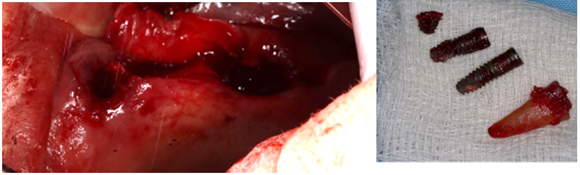

Step 1: Removal of Failed Implants at The Upper Jaw

Figure 3: Extraction of failed implants and roots.

Figure 4: Panoramic after removing failed implants and roots.

The treatment is done by complete enucleation of the cyst via palatal approach under local anesthesia. Palatal incision was performed and detachment of palatal mucosa in the region between the right and left canines approximately. Dissection was performed between the cystic capsule and the adherent mucosa, followed by cyst enucleation and cleaning of the cavity. The flap was sutured with 3/0 silk.

Figure 15: Incision and removal of the cyst.

Figure 16: Size of the cyst.